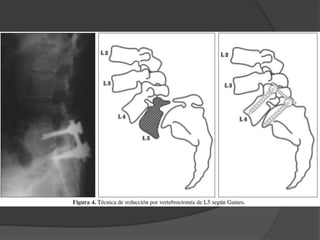

 Espondilolistesis deAlto Grado - Artrodesis in situ - Descompresión y artrodesis posterior - Reducción artrodesis 360 - Resección de L5 y APL L4 – S1

 Espondilolistesis de Alto Grado

- Artrodesis in situ

- Descompresión y artrodesis posterior

- Reducción artrodesis 360

- Resección de L5 y APL L4 – S1